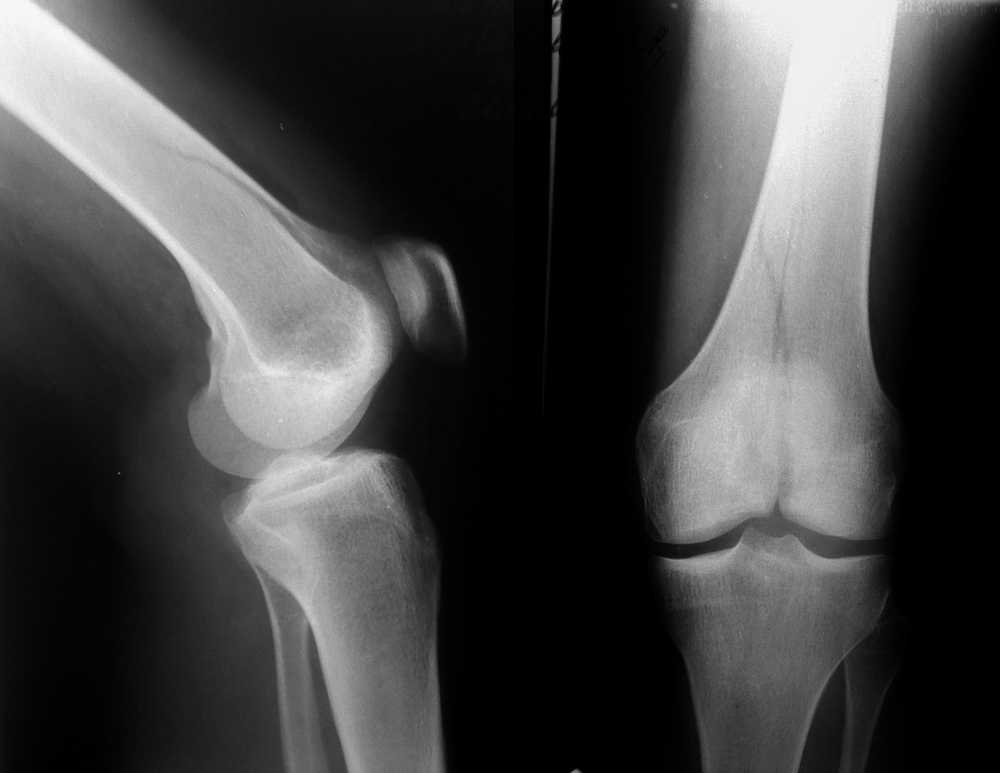

Межмыщелковый перелом бедра

Перелом медиального мыщелка правой бедренной кости, по классификации Мюллера - 33-В2.1

Женщина, 24 года, травма в быту, при падении с лестницы на согнутое колено.

Кожные покровы в хорошем состоянии, гемартроз умеренный, повреждения крестообразных связок пока не видно.

По снимкам имхо не очень понятно, где же на самом деле заканчивается линия перелома.

Можно засунуть хорошую конструкцию, а потом быть "приятно удивленными" неожиданным продолжением линии перелома.

Внутрисуставной, простой перелом у молодой пациентки с хорошим качеством кости требует: во-первых, анатомичной репозиции, что в данном случае при небольшом смещении не должно вызвать затруднений, во-вторых, межфрагментарной компресии посредством стягивающих винтов для достижения абсолютной стабильности. Пластина, которая бы эффективно дополняла бы стягивание винтами, как нейтрализующая или противоскользящая, должна быть установлена по медиальной воверхности, что в данном случае на бедре малоприемлимо ввиду анатамических особенностей и трудности доступа. Пластина клинковая, или мыщелковая, или DCS, установленные снаружи, не будет выполнять этой функции. Штифты вообще не показаны при переломах 33.В..